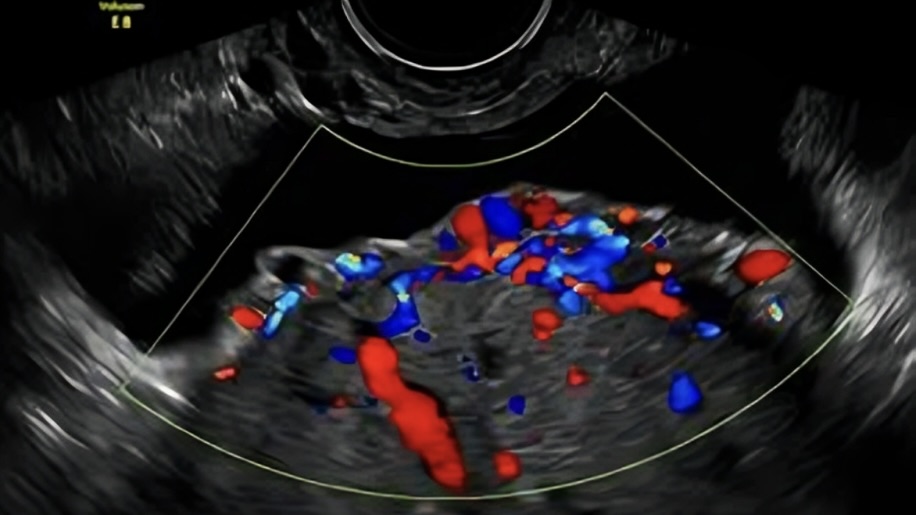

A 34-year-old woman, G3P2, with two previous cesarean sections, attends her 22-week ultrasound scan. She reports no other uterine surgeries.

Look at the images below.

What is the most appropriate interpretation of these findings?

A. Normal findings in placenta previa after previous cesarean section.

B. Suspicion of placenta accreta spectrum disorder requiring referral to a specialised PAS centre.

C. Isolated placental lakes without clinical significance.

D. Indication for immediate delivery due to high risk of uterine rupture.